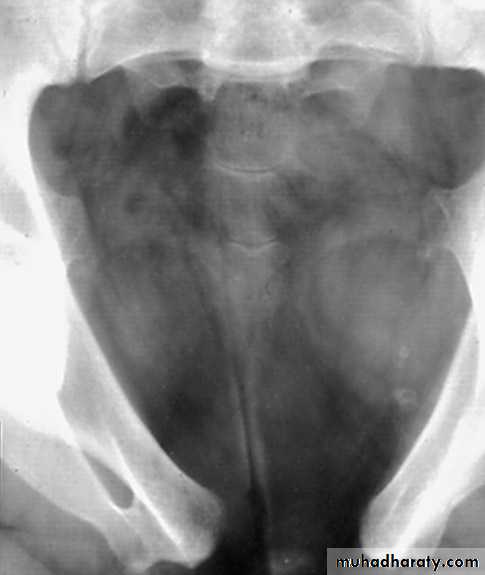

Ureterocele :

Congenital cystic dilatation of lower end of ureter ( intra-mural part) due to pin-hole meatus . May be simple or ectopic .

simple : the orifice is in proper position of bladder ,

Ectopic >> in bladder neck , urethra , uterus & vagina .

IVU :

- There is rounded or elliptical dilatation of lower end of ureter with thin lineal filling defect around it , resembling (cobra head appearance),

- Proximal dilatation of rest of ureter .

- In advanced cases hydronephrosis .

- In obstructed ureterocele , filling defect in the bladder